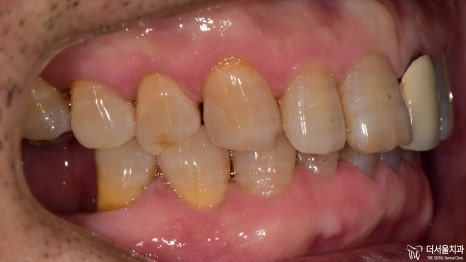

구강 상태가 좋지 않았지만

시간, 비용 여러 면에서 상황이 좋지 않아

계속해서 내원을 미뤄오셨다던 환자분.

처음에는 한두 곳의 문제로 시작되었지만

나중에는 걷잡을 수 없이 퍼졌다는데요.

이제 결과를 보여드릴 차례네요.

모든 보철을 지르코니아를 사용하여

심미성을 한껏 더해주었습니다.

이렇게 몇 곳만 바뀌어도

가만히 있던 주변 치아들까지

좀 더 건강하고 활기차 보이지 않나요?